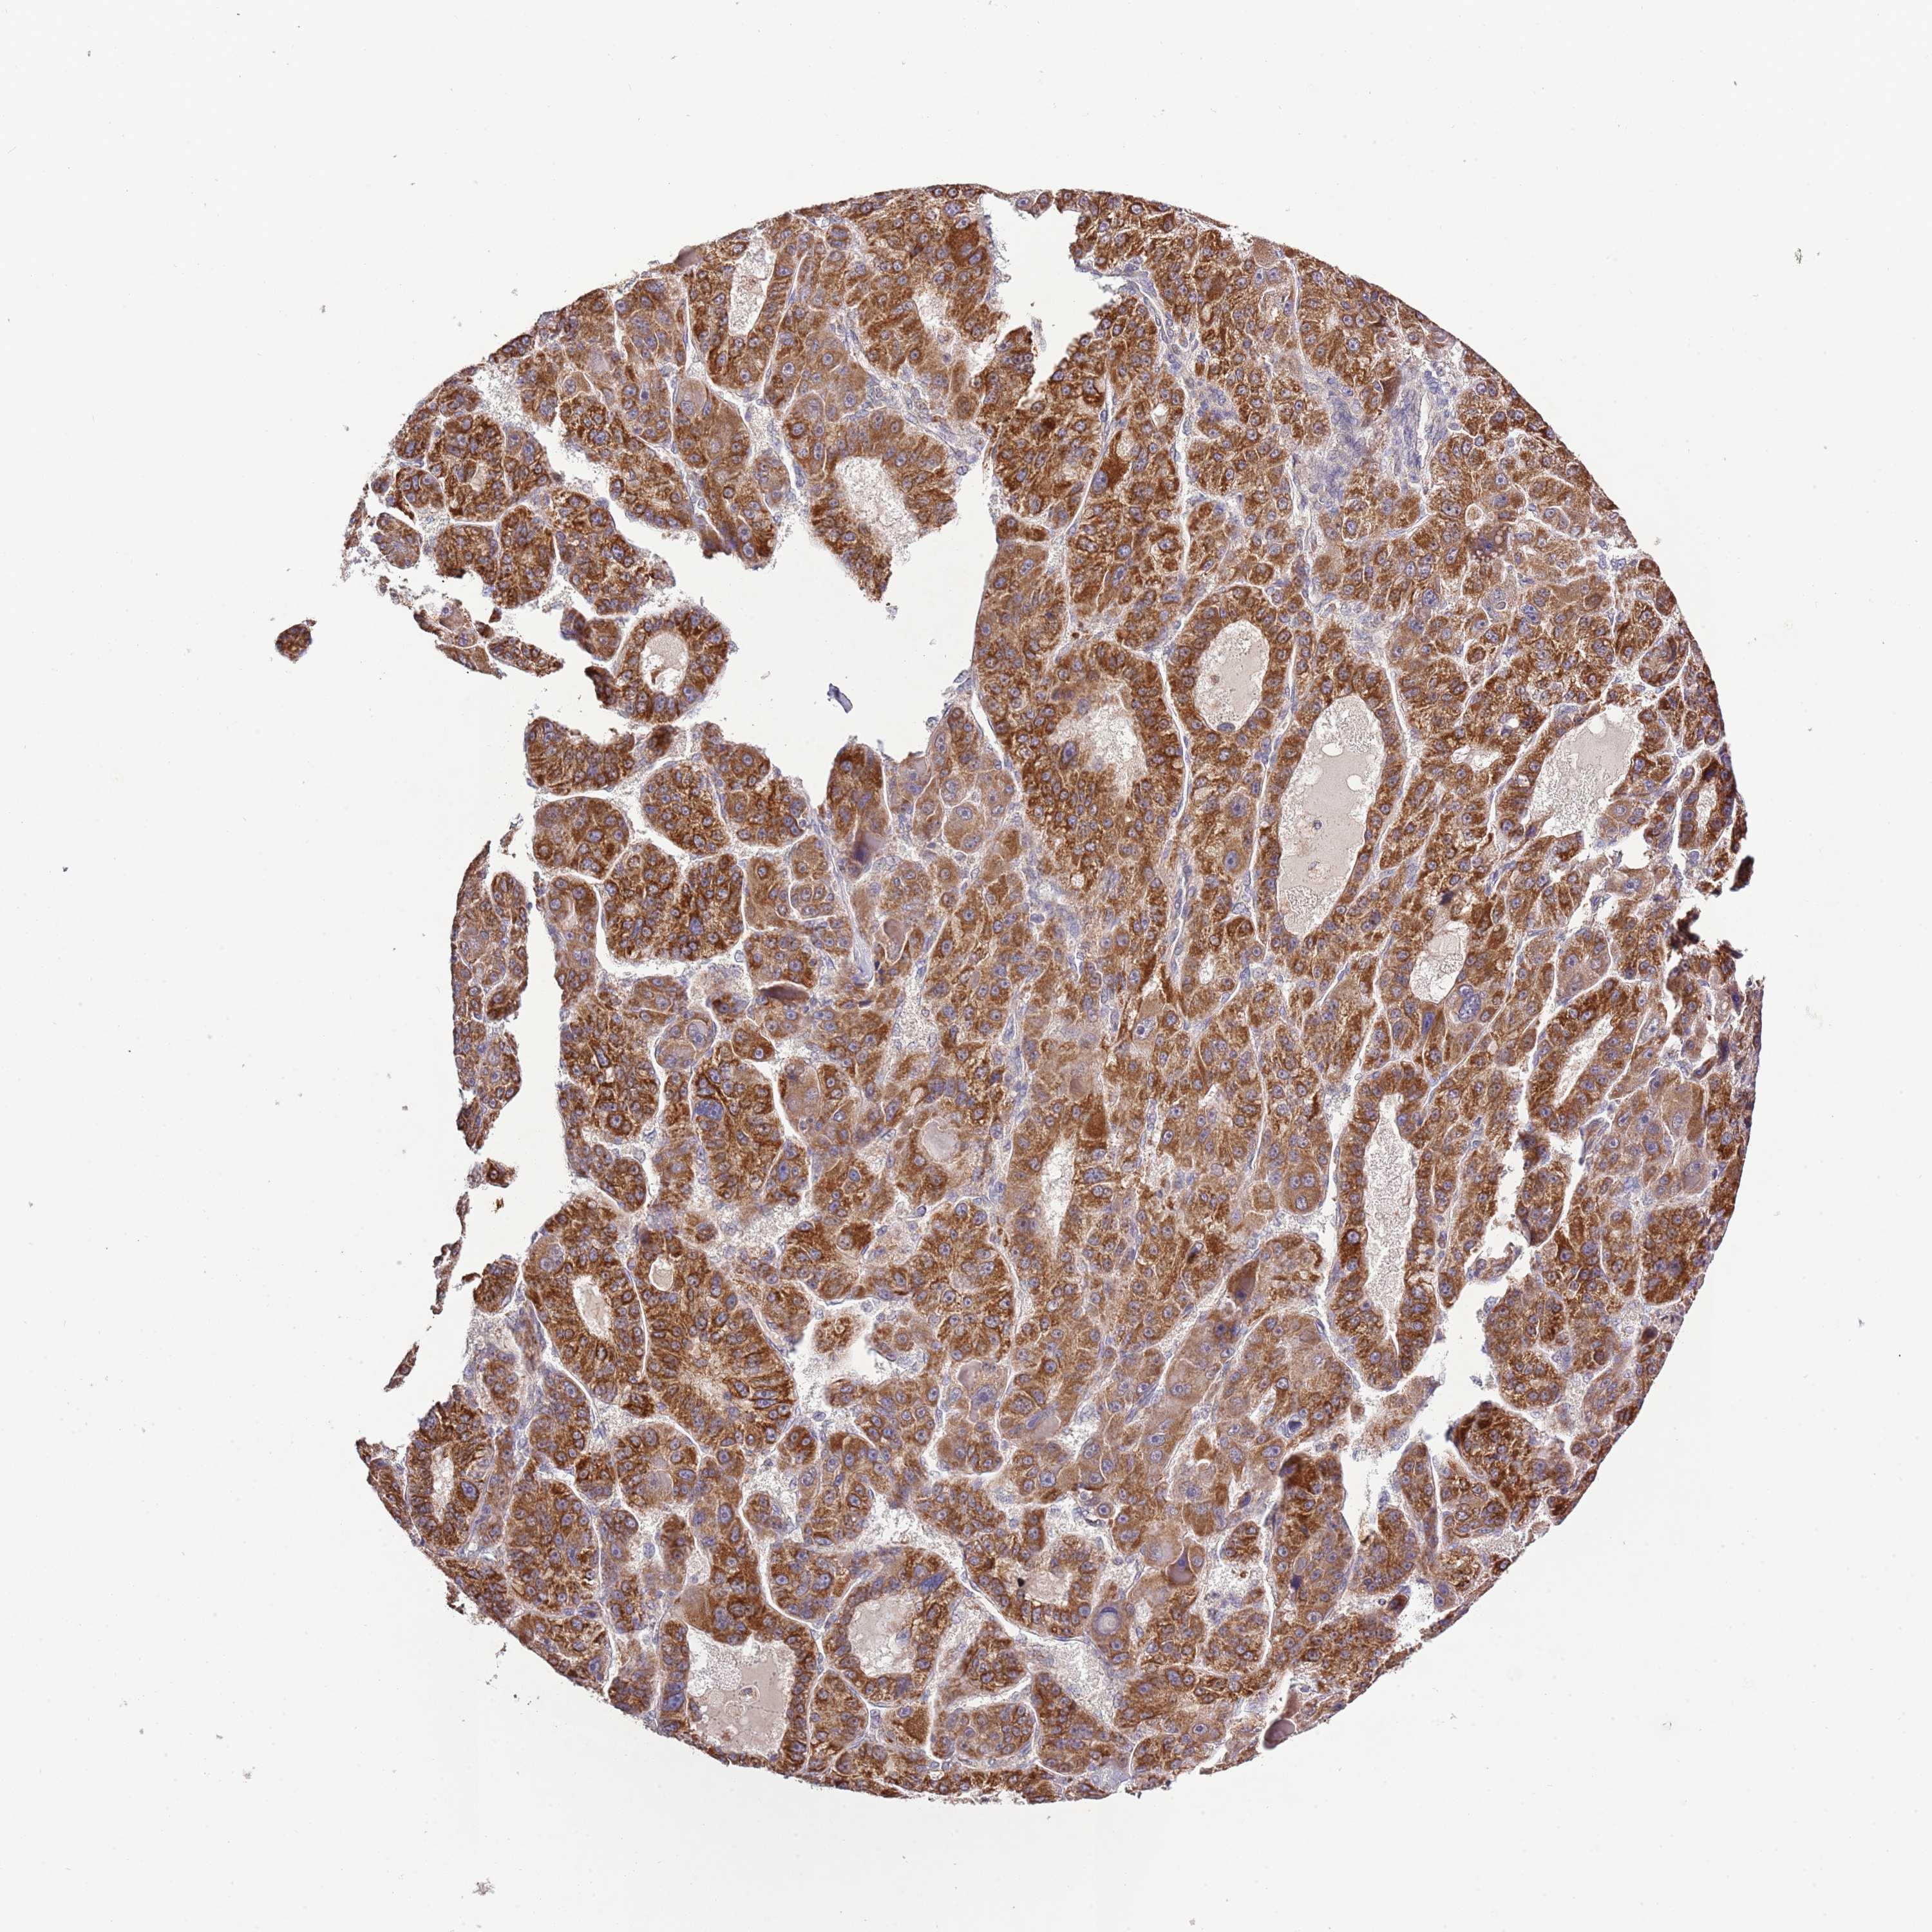

LIVER CANCER - Protein expressioni

A mouse-over function shows sample information and annotation data. Click on an image to view it in a full screen mode. Samples can be filtered based on level of antibody staining by selecting one or several of the following categories: high, medium, low and not detected. The assay and annotation is described here.

Note that samples used for immunohistochemistry by the Human Protein Atlas do not correspond to samples in the TCGA dataset.

Antibody stainingi

Antibody staining in the annotated cell types in the current human tissue is reported as not detected, low, medium, or high, based on conventional immunohistochemistry profiling in selected tissues. This score is based on the combination of the staining intensity and fraction of stained cells.

Each image is clickable and will lead to virtual microscopy that enables deeper exploration of all samples and also displays staining intensity scores, fraction scores and subcellular localization as well as patient and tissue information for each sample.

Antibody HPA041391

Antibody HPA044250

Staining

High

Medium

Low

Not detected

Intensity

Strong

Moderate

Weak

Negative

Quantity

>75%

75%-25%

<25%

None

Location

Nuclear

Cytoplasmic/membranous

Cytoplasmic/membranous,nuclear

Cholangiocarcinoma

Carcinoma, Hepatocellular, NOS